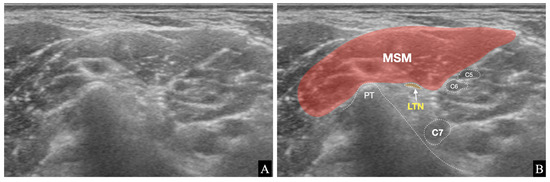

2.1. Ultrasound Image

indicates that it was outside the risk area in the simulated risk analysis. The LTN’s mean location and locational area estimated by the mean ± standard deviation (SD) are presented. The painted area indicates that the needle’s trajectory is expected to be associated with a high risk of LTN injury.